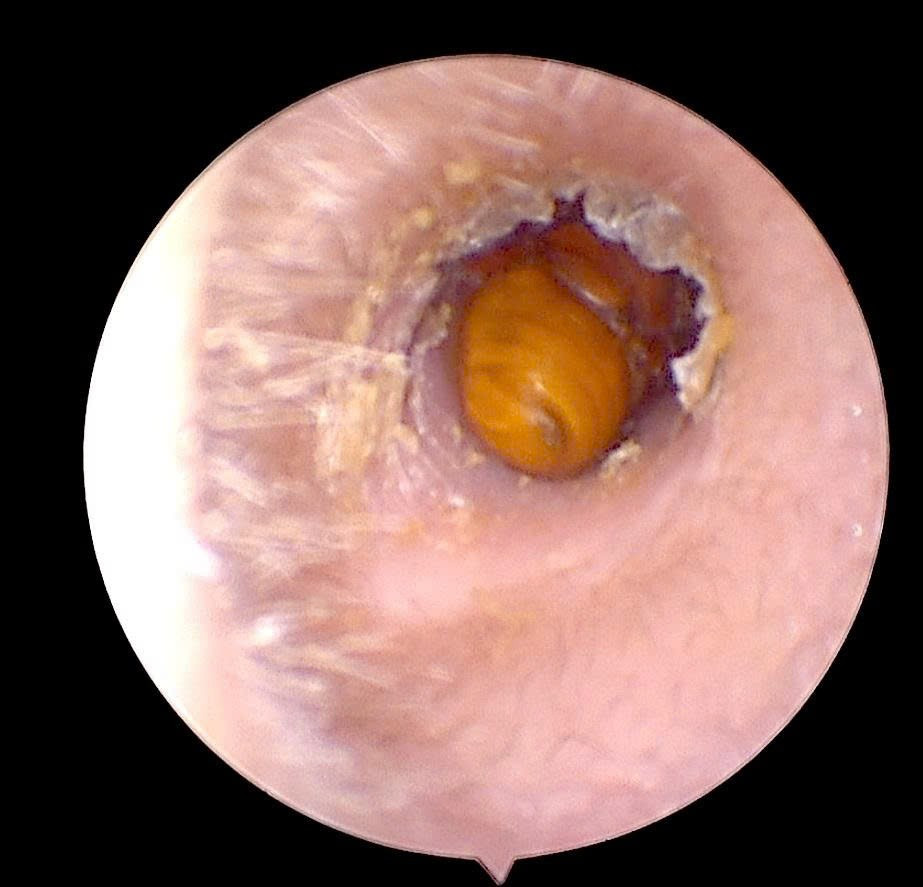

Ngay sau khi xác định vị trí dị vật, bác sĩ đã tiến hành lấy dị vật dưới nội soi với thao tác cẩn trọng, an toàn, tránh làm tổn thương thêm màng nhĩ.

Quá trình xử trí diễn ra nhanh chóng, dị vật được lấy ra hoàn toàn, tai được làm sạch và kiểm tra lại tổn thương. Hiện bệnh nhân đã ổn định, giảm đau và nghe rõ hơn, được hướng dẫn chăm sóc, theo dõi phục hồi tại nhà.

Con côn trùng được lấy ra thành công - Ảnh BVCC